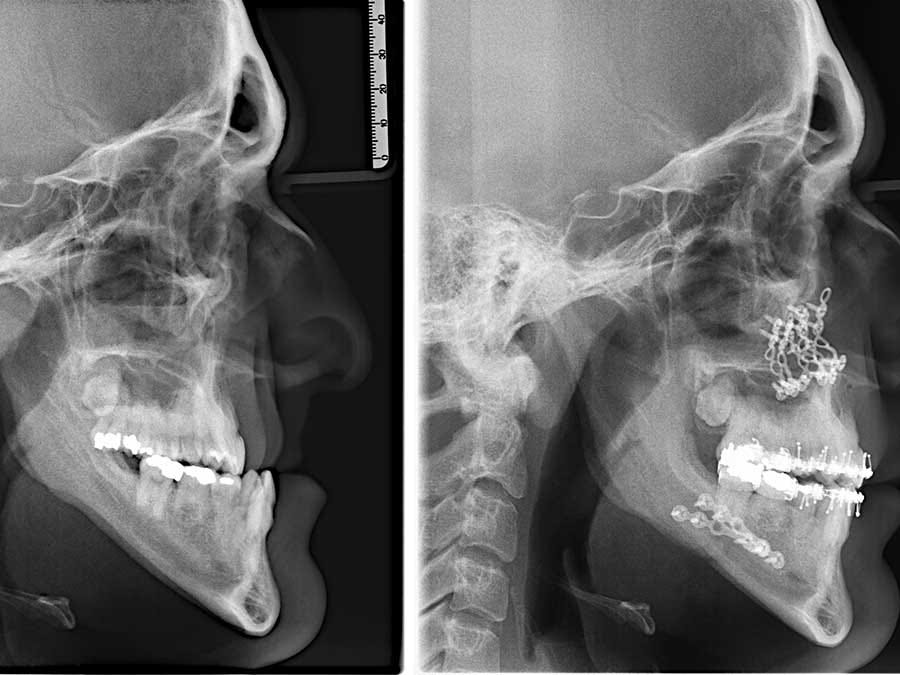

我在許多顳顎關節討論社團裡看到,很多人熱烈地討論著要去做下巴手術。他們以為只要透過手術把下巴移到「正確」的位置,所有問題就能迎刃而解。有些人甚至被醫生告知,手術是他們「唯一的選擇」。

但我要直說了 —— 這完全是胡說八道。我在這個領域也有十年了,追蹤過相當多為了治療顳顎關節問題而去動手術的人(他們做手術可不是為了變漂亮)。結果呢?手術之後他們或許短暫覺得好轉…撐上一兩年也許沒問題。但最終,某個時間點他們發現自己又回到了原點。為什麼?因為他們根本沒有解決真正的問題。

手術改變不了軟組織。

外科醫生們不明白一件事:光靠移動骨頭,解決不了這個問題。包覆在你顱骨周圍的軟組織,就好比一顆洩了氣的氣球。當你動手術時,你不過是在那顆癟掉的氣球裡重新擺弄骨頭的位置罷了。但你想想,軟組織最終還是會把一切拉回原來的位置。

你有沒有注意過那些十幾年前做過拉皮手術的人?過去七八年,我特別留心觀察這種例子。他們後來看起來幾乎都怪異至極,極不自然。為什麼?因為軟組織把本來鬆弛的部分又全都拉回去了!而這正是那些外科醫生不想讓你知道的真相。這就是物理現象的威力,你不可能用鋸開骨頭、上螺絲釘的方式來對抗物理法則。

我自己每天在做伸展練習時,真的彷彿在硬生生撕開臉部和頭皮下的那些軟組織。(在我之前發表的另一篇文章〈那塊神祕的拼圖碎片是……軟組織〉中,我詳細談過這件事。)只有靠這種方式,你才能帶來永久性的改變。這可不是讓某個外科醫生幫你把下巴移動幾毫米、然後鎖上幾根鋼釘就能達成的。